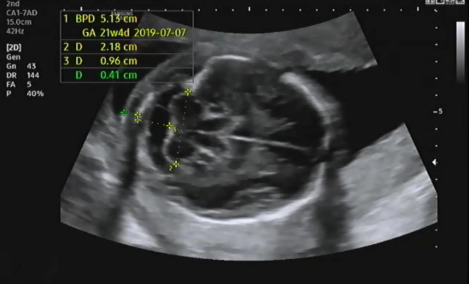

그다음 태아의 머리 둘레를 측정하고 21주 차에 맞게 뇌가 주수에 알맞게 발달하였는지, 물혹 등의 여부나 기형이 있는지 확인을 한다.